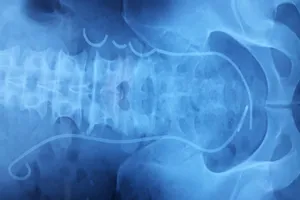

Ống thông đứt làm 3, bị 'bỏ quên' trong niệu quản suốt 3 năm